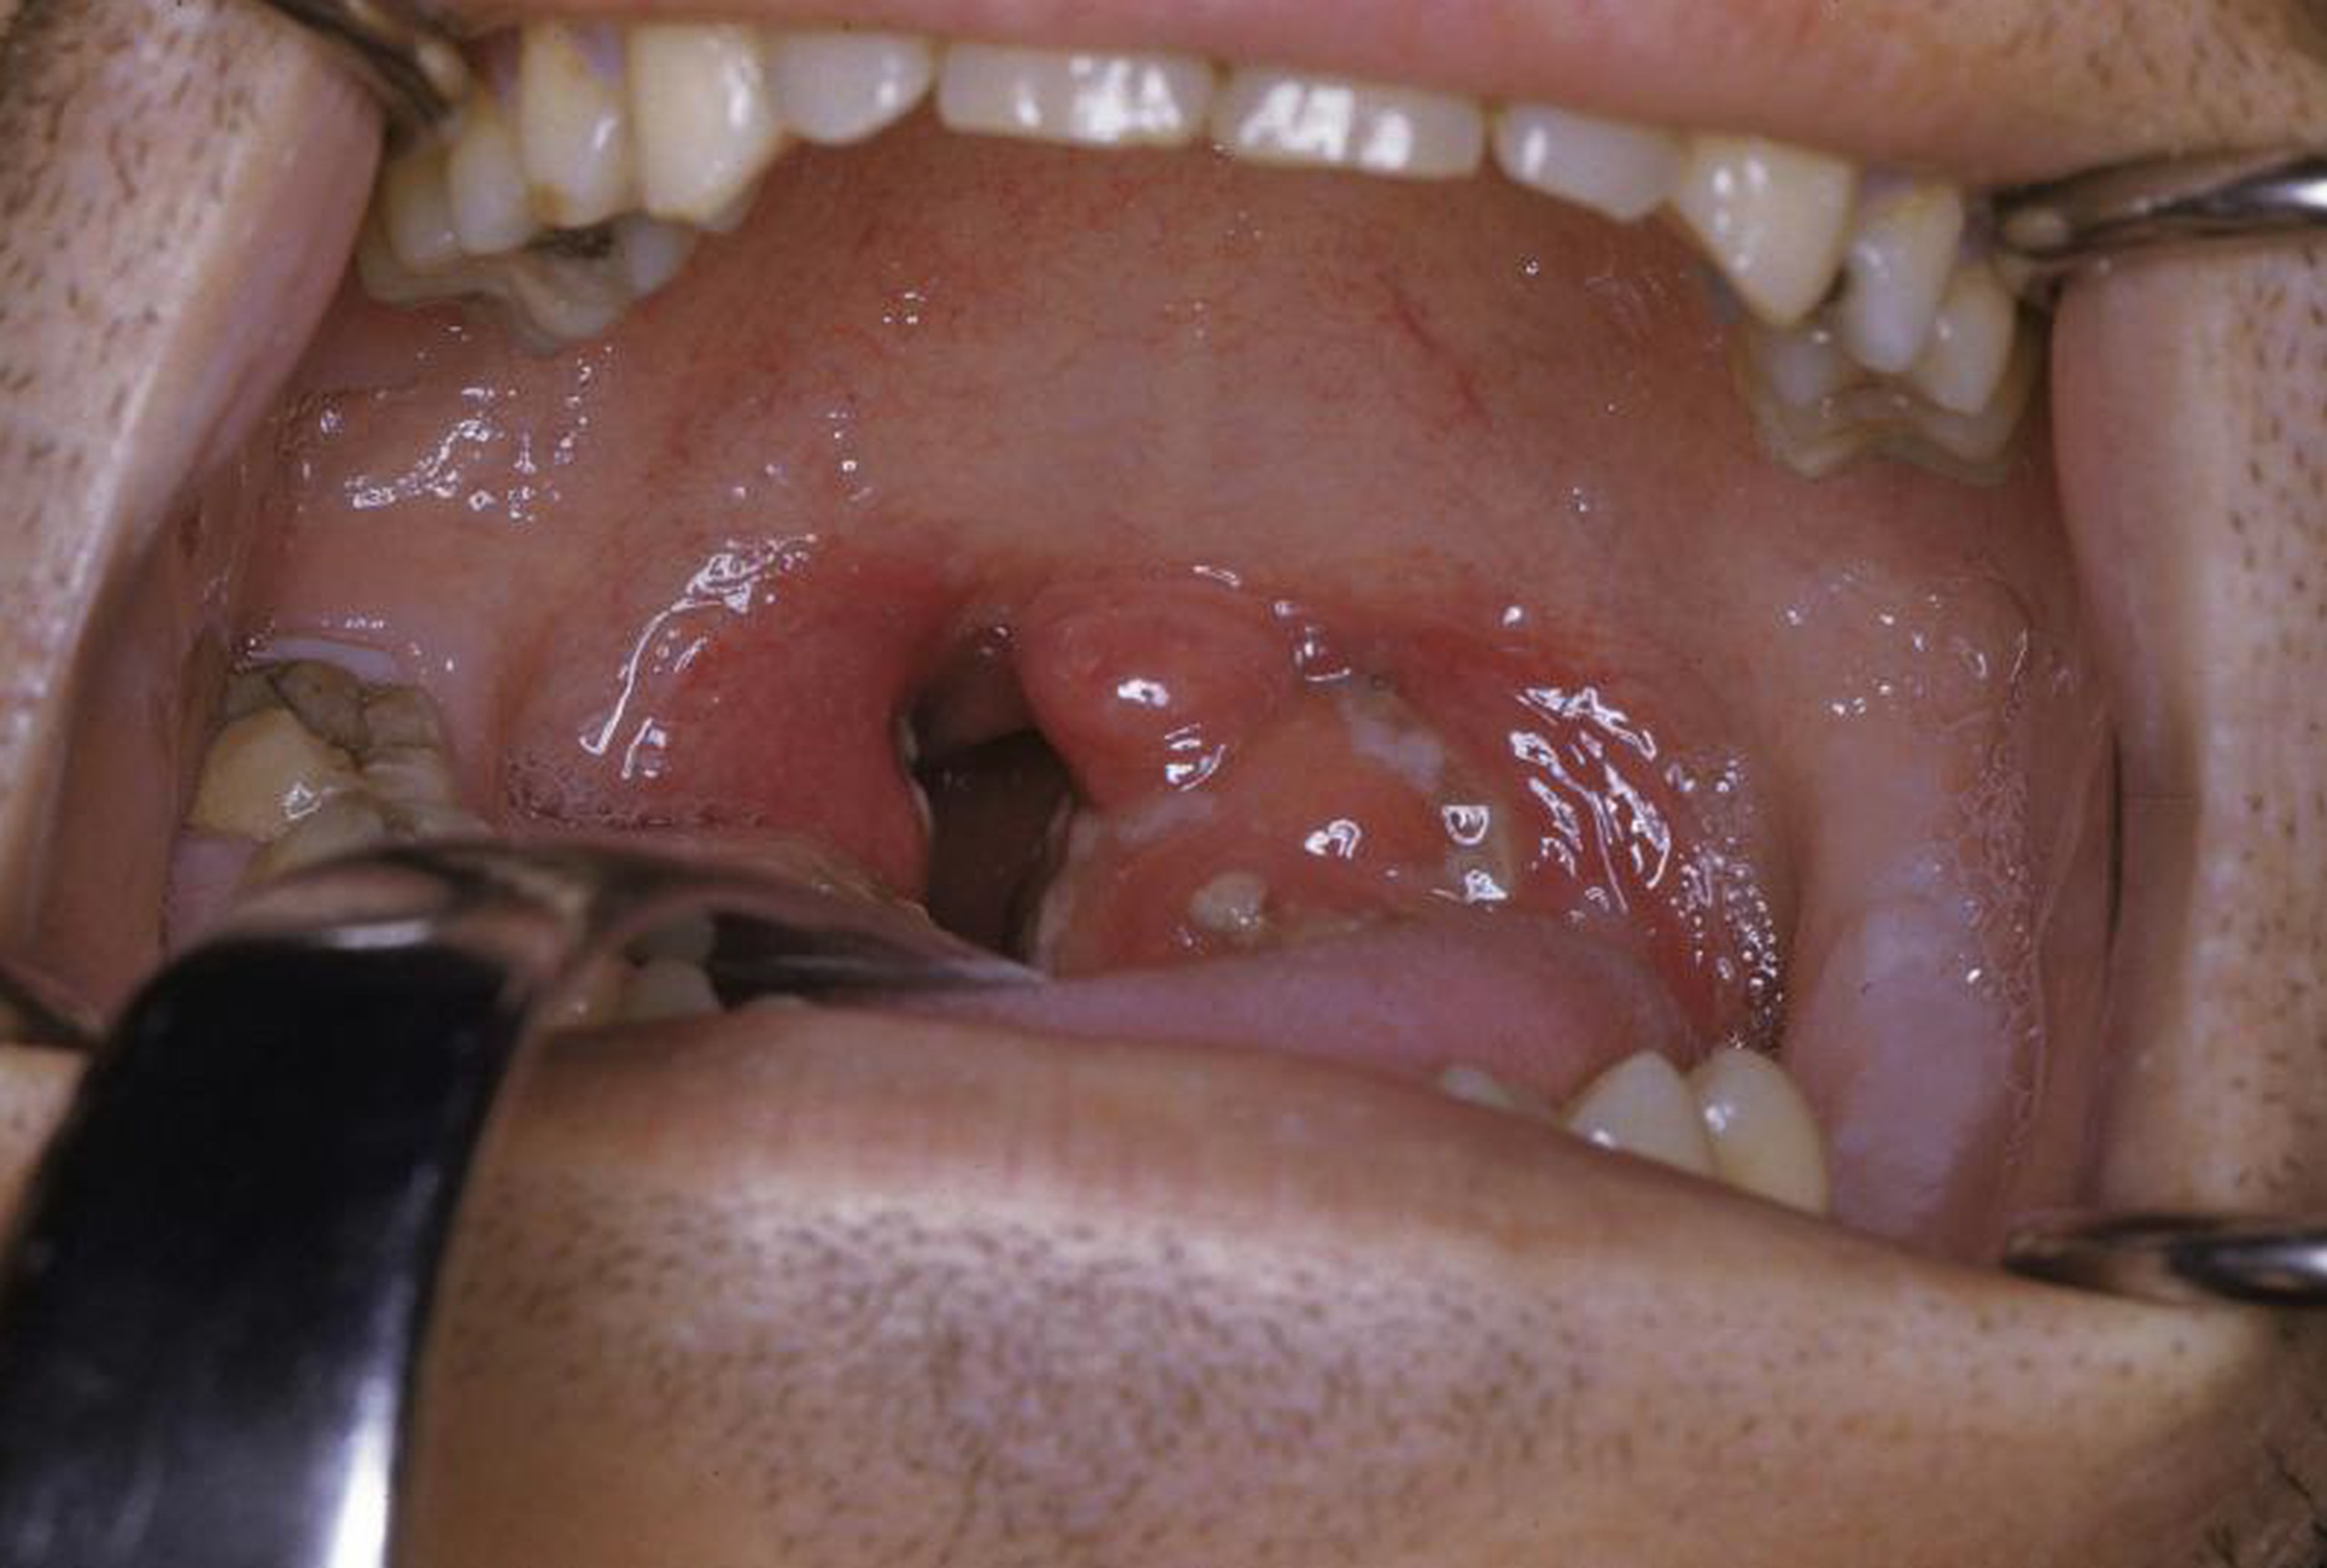

Viêm amidan là tình trạng nhiễm trùng cấp tính ở họng, amidan vòm họng hoặc cả hai. Các triệu chứng có thể bao gồm khó nuốt, đau họng, nổi hạch cổ và sốt. Chẩn đoán dựa trên lâm sàng, cận lâm sàng bao gồm nuôi cấy hoặc xét nghiệm kháng nguyên nhanh. Việc điều trị phụ thuộc vào các triệu chứng và trong trường hợp nhiễm β- Streptococcus tan huyết nhóm A, cần dùng đến thuốc kháng sinh.

Viêm amidan là tình trạng tuyến amidan bị tổn thương, viêm nhiễm cấp tính hoặc mạn tính. Viêm amidan do vi khuẩn hoặc virus gây ra. Khi vi khuẩn tấn công ồ ạt vào mũi họng sẽ làm amidan làm việc quá mức dẫn đến amidan bị sưng, đỏ và đau.

Amidan là hàng rào miễn dịch đầu tiên của hệ hô hấp, sau khi chống lại vi khuẩn, xác vi khuẩn, bạch cầu và mô hoại tử có thể tích tụ ở amidan tạo thành cục mủ có mùi hôi, thường gặp trong viêm amidan mạn tính.

Các triệu chứng bao gồm khó chịu, sốt cao, nhức đầu, rối loạn tiêu hóa cũng như chứng hôi miệng và giọng nói bị nghẹt. Phát ban cũng có thể có thể xảy ra. Amidan sưng tấy, đỏ và thường xuyên có dịch mủ. Có thể có sưng đau hạch cổ. Sốt, nổi hạch, ban xuất huyết vòng họng và vỡ mủ thường là dấu hiệu phổ biến của viêm họng do liên cầu tan huyết β nhóm A (GABHS) hơn là với viêm amidan do virus, nhưng cũng có nhiều điểm trùng lặp. Với GABHS, có thể xuất hiện phát ban dạng scarlatiniform (ban đỏ).